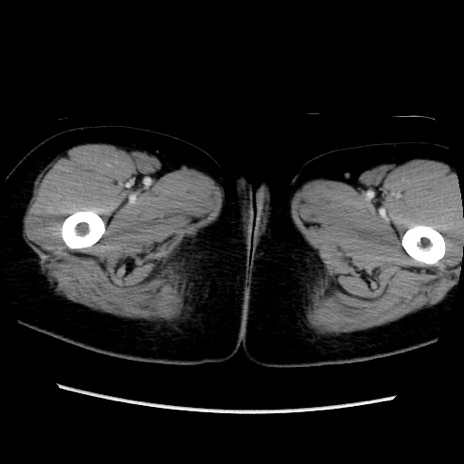

MRI(4日後)